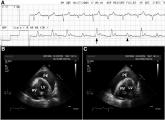

ArticleElectrical Alternans and Pulsus ParadoxusAuthor:Ernest Lo, MDPublish date: April 8, 2010Read More